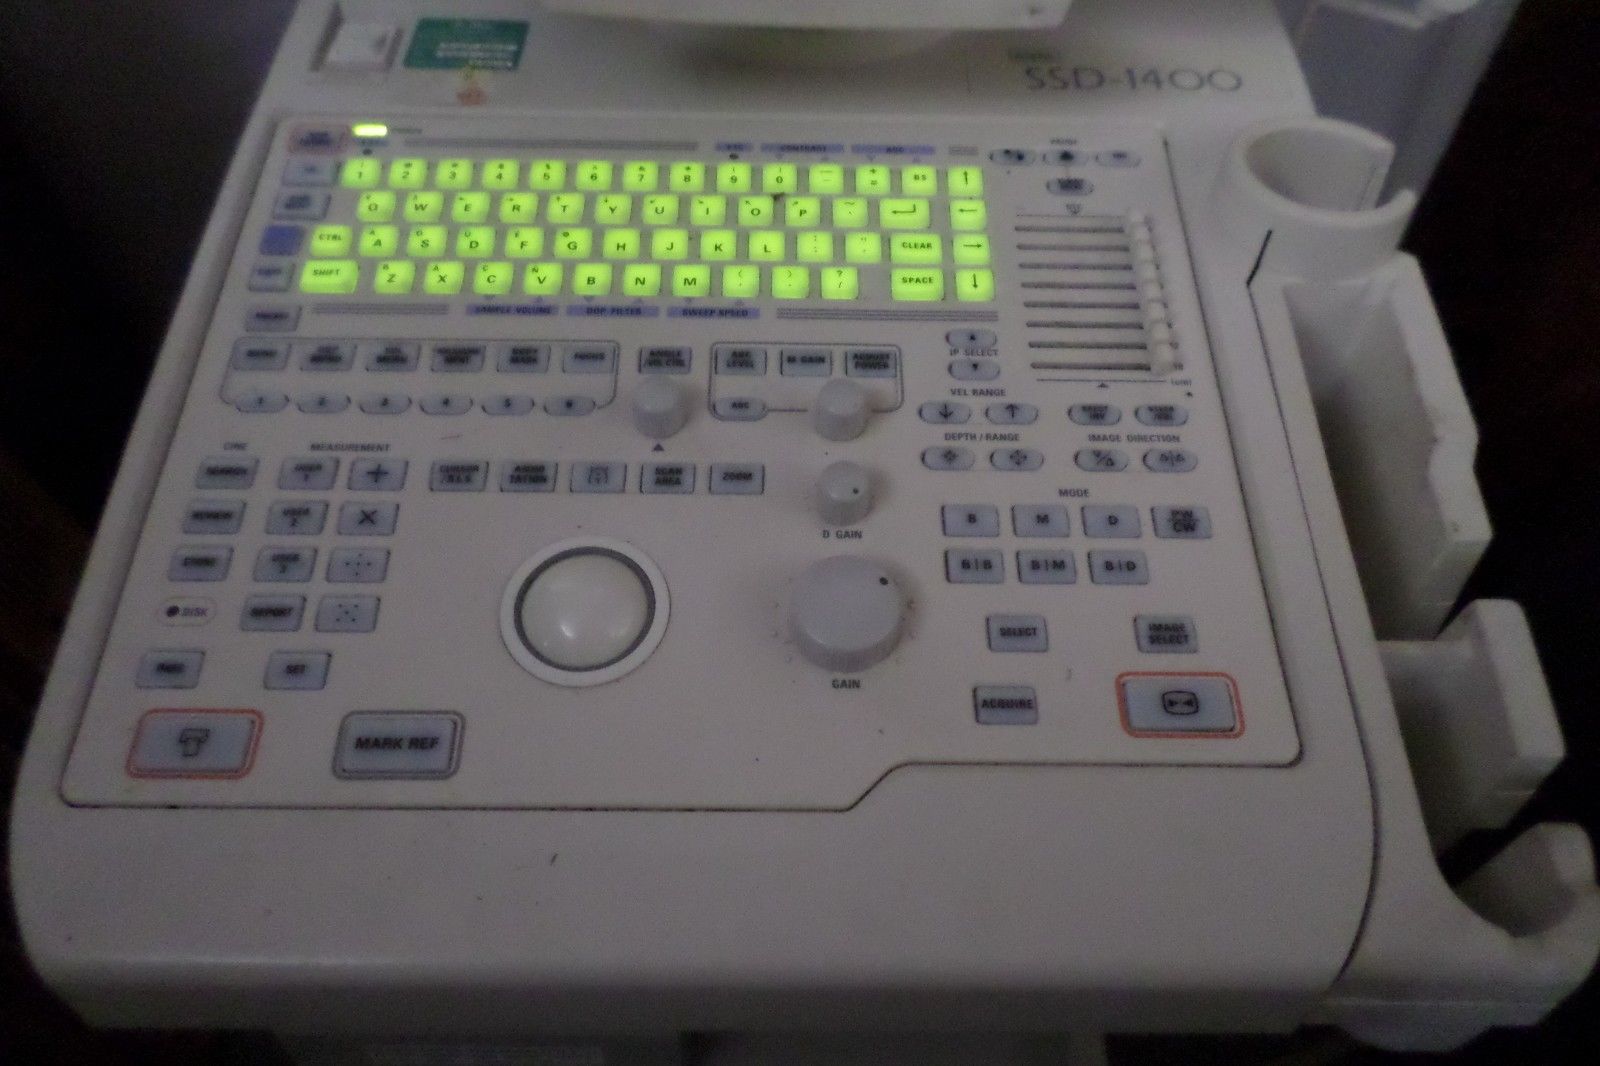

DIAGNOSTIC ULTRASOUND MACHINES FOR SALE

DIAGNOSTIC ULTRASOUND MACHINES FOR SALE

DIAGNOSTIC ULTRASOUND MACHINES FOR SALE